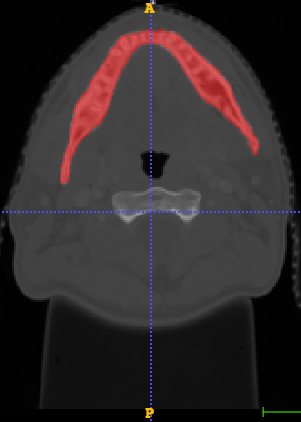

In Chapter 6, we propose an end-to-end, atlas-free 3D convolutional deep learning framework for fast and fully automated whole-volume HaN anatomy segmentation [115]. Our deep learning model, called AnatomyNet, segments OARs from head and neck CT images in an end-to-end fashion, receiving whole-volume HaN CT images as input and generating masks of all OARs of interest in one shot. AnatomyNet is built upon the popular 3D U-net architecture, but extends it in three important ways: 1) a new encoding scheme to allow auto-segmentation on whole-volume CT images instead of local patches or subsets of slices, 2) incorporating 3D squeeze-and-excitation residual blocks in encoding layers for better feature representation, and 3) a new loss function combining Dice scores and focal loss to facilitate the training of the neural model. These features are designed to address two main challenges in deep-learning-based HaN segmentation: a) segmenting small anatomies (i.e., optic chiasm and optic nerves) occupying only a few slices, and b) training with inconsistent data annotations with missing ground truth for some anatomical structures. We collect 261 HaN CT images to train AnatomyNet, and use MICCAI Head and Neck Auto Segmentation Challenge 2015 as a benchmark dataset to evaluate the performance of AnatomyNet. The objective is to segment nine anatomies: brain stem, chiasm, mandible, optic nerve left, optic nerve right, parotid gland left, parotid gland right, submandibular gland left, and submandibular gland right. Compared to previous state-of-the-art results from the MICCAI 2015 competition, AnatomyNet increases Dice similarity coefficient by 3.3% on average. AnatomyNet takes about 0.12 seconds to fully segment a head and neck CT image of dimension , significantly faster than previous methods. In addition, the model is able to process whole-volume CT images and delineate all OARs in one pass, requiring little pre- or post-processing. We demonstrate that our proposed model can improve segmentation accuracy and simplify the auto-segmentation pipeline. These contributions are released as an open-source software package called AnatomyNet, which is publicly available555https://github.com/wentaozhu/AnatomyNet-for-anatomical-segmentation. Portions of this chapter were published as part of [115].